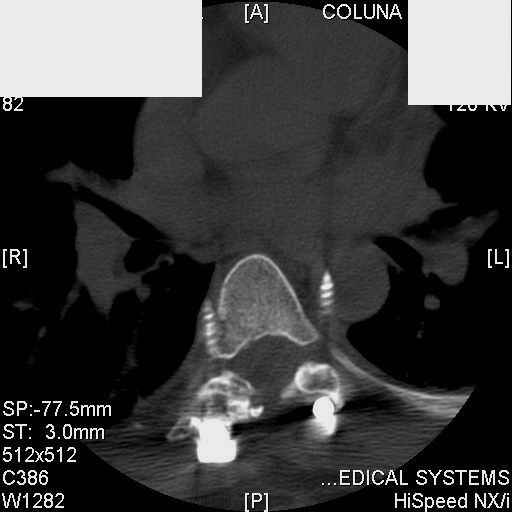

Interesting case. Findings on CT: all four pedicle screws have been placed improperly inthat they miss the vertebral bodies. In addition, the screws on the left side are impingingon the decending thoracic aorta. What I do NOT know is the nature of the original injury, orwhether or not that injury has resolved. I would recommend removal of the hardware. I don'tthink it's a good idea to leave those screws where they are. If the original fracture ishealed, nothing else needs to be done.

dear Mark, all the details are not yet available but the patient is coming to see us foradvice. We probably will see him in the early new year. i thought that the 4th picture showedthe screw to enter the aorta? He is a victim of a motor vehicle crash and thoracic vertebralfracture which appears healed. He was posteriorly decompressed and this device inserted. asyou say there isno evidenece that any of the fixation enters the bodies via the pediclesistead they have passed thru and their end are no where near where they ought to be. If I amcorrect (I would prefer not to be) the aortic intima has been breached by the screw. When thetime comes to take the screw out I thought we should have control of the aorta.What do you think?

Tom: I strongly doubt that the aorta is involved. When these screws are put in, they firstput in a probe, then a tap, then the screw. If the aorta was punctured, they would have knownat the time. You might call the original surgeon (if in fact he is a real doctor) and get hisfeedback. The additional morbidity of a prophylactic thoracotomy would be a higher pricethan I would be willing to subject my patient to. Besides, it would be exceptionallydifficult to control the aorta at this point, especially if you tried to specifically getenough control to be able to put sutures in the back wall. Of course, difficulty of doingsomething isn't necessary a reason not to do it if you think it is necessary. I just think itis highly unlikely that the aorta is injured. I showed the case to both a thoracic surgeon anda neurosurgeon. The thoracic surgeon suggested getting an arteriogram to see if the aorta isinvolved. The neurosurgeon agreed that the hardware should be removed.

Mark Thank you. He is scheduled for a angio prior to transfer here. I keep going back to lookat that fourth image and although it is tough to believe the wall of the aorta seems toencompass the distal 1/2 of the screw. I have come to anticipate mal postion of screws thathave been inserted in hospitals that perhaps may not have the highest quality of equipment,including the human and radiological components. That having been said this case seems tosurpass the usual... one screw out of place or screwed into a disc etc. BTW I am notsuggesting that the screw was placed directly into the aorta but that moviment, pulse actionetc may have caused it to transgress the normal anatomical bounds without evident hemorrhage.